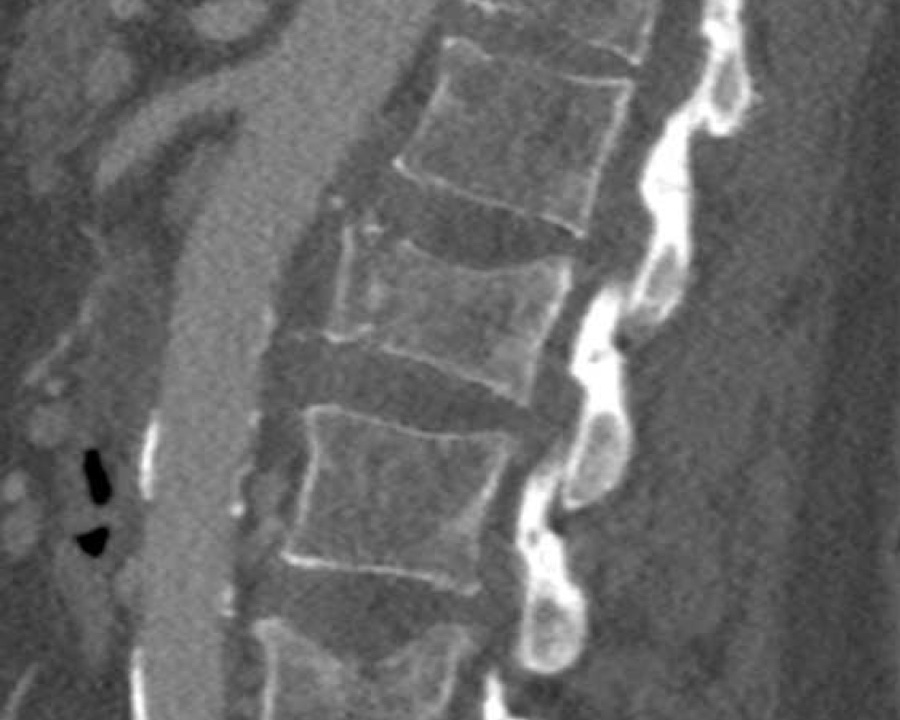

A2 Split fracture

A2 is a fracture of both endplates without involvement of the posterior wall of the vertebral body.

What is the highest AO-type of injury?

Findings:

- No C or B injury

- Fracture of the vertebral body with involvement of both endplates (1+1 points), no posterior wall involvement

Conclusion

injury type A2